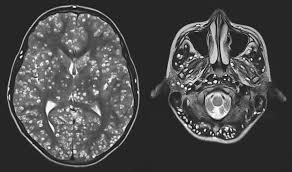

El caso de un joven atendido por fuertes dolores de cabeza y convulsiones reveló una enfermedad conocida como neurocisticercosis, provocada por larvas del parásito Taenia solium.

Estas larvas se alojan en el cerebro, causando inflamación, daño neuronal y, en casos graves, convulsiones o la muerte.